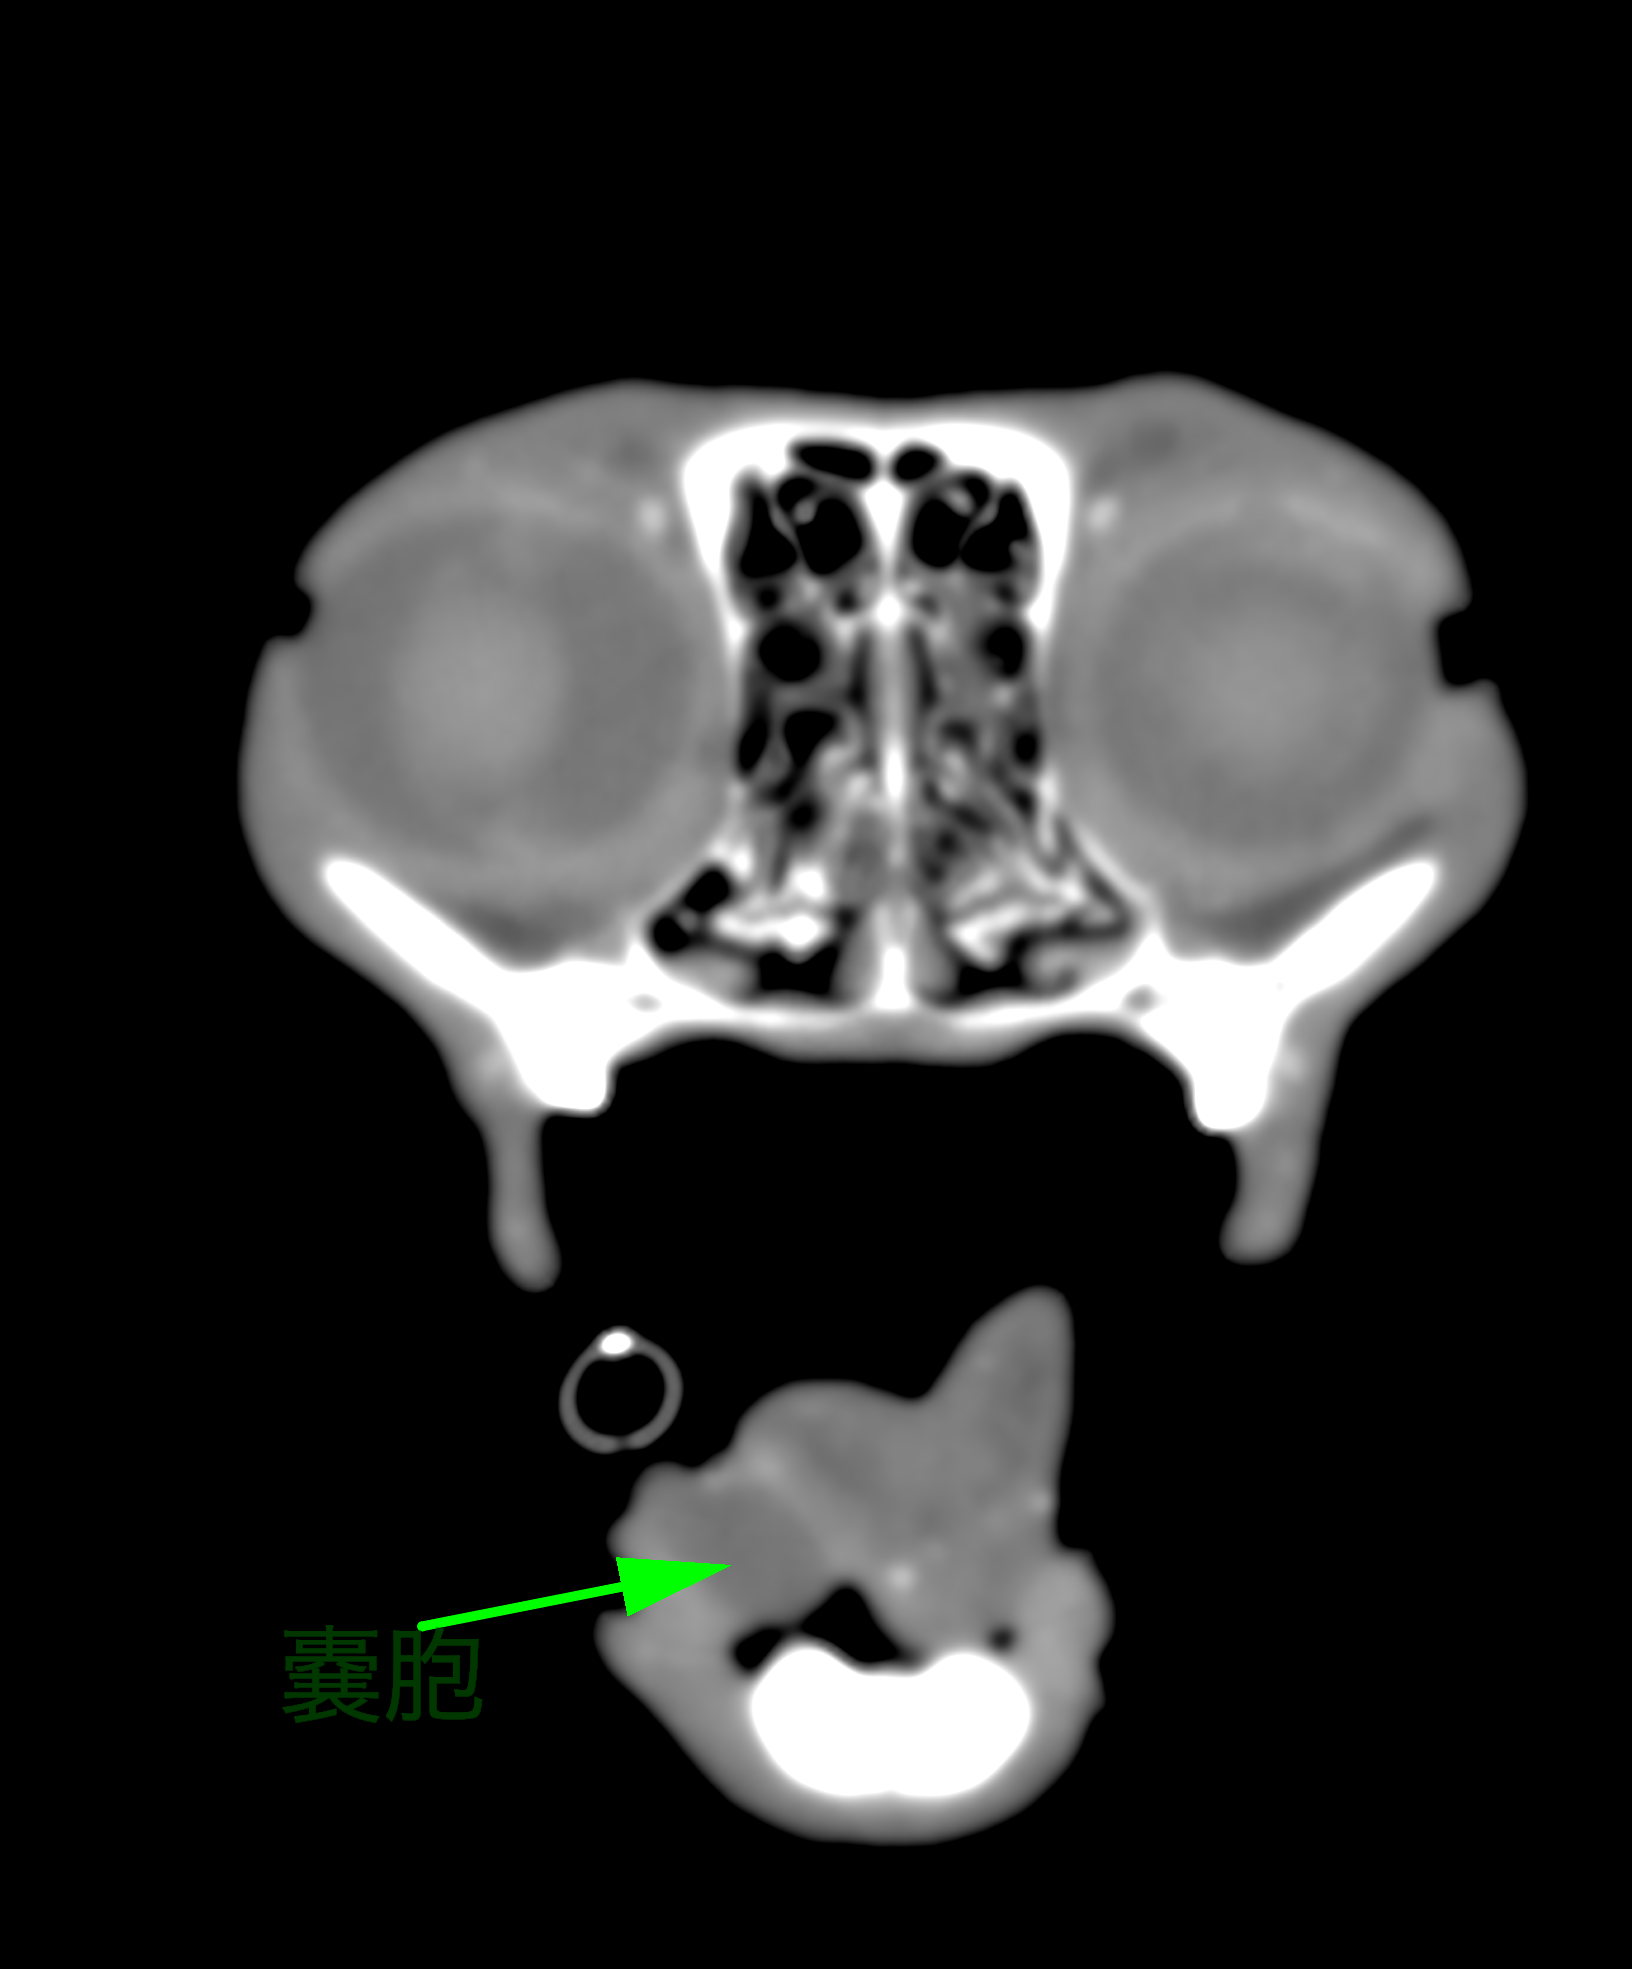

※緑矢印は唾液瘤です

【CT画像検査】 CT画像検査では唾石がないことが確認されました。また今回の唾液瘤の原因として下顎腺と舌下腺が疑わしいという結論に至りました。

※CT画像検査写真です